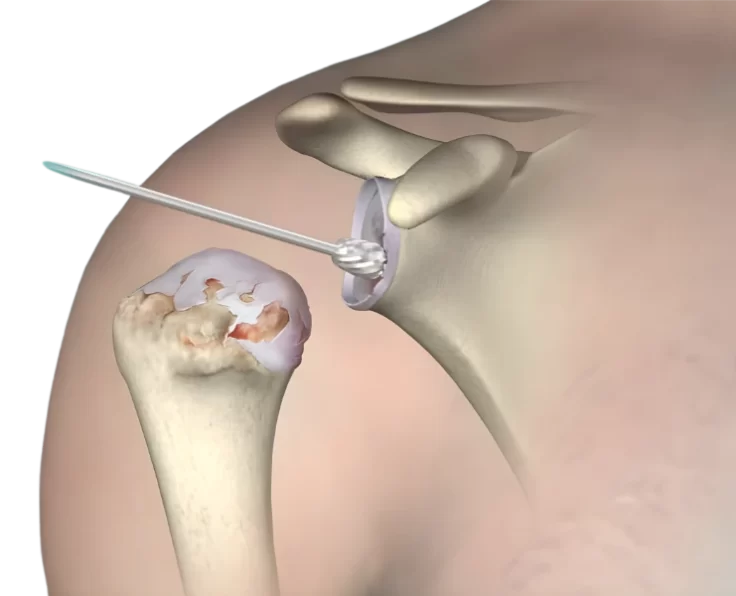

Shoulder Arthroscopy

Arthroscopy is a procedure used by orthopaedic surgeons to evaluate and treat joint conditions. A shoulder arthroscopy procedure is commonly performed to relieve pain and…